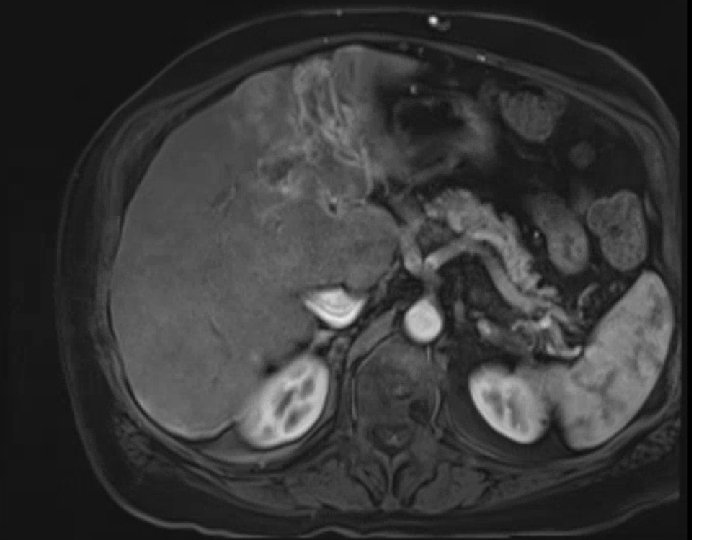

Pre-presentation MRI